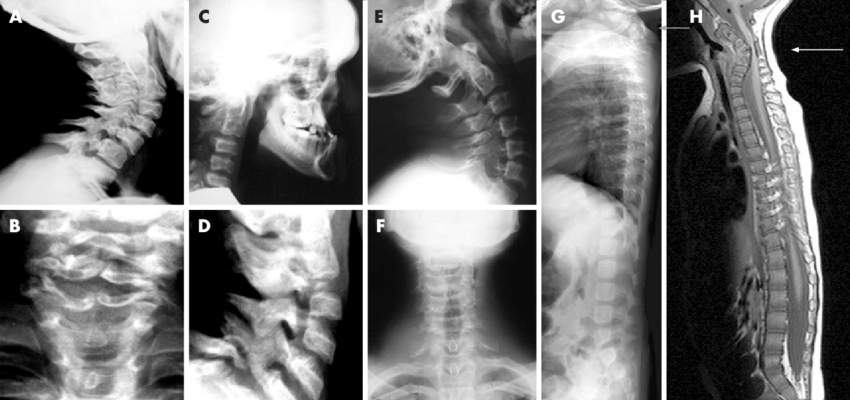

Um das HWS-Syndrom zu diagnostizieren, führt der behandelnde Arzt zunächst eine körperliche Untersuchung durch: Hierbei wird die Bewegung und Funktionalität der Wirbelsäule und der Zwischenwirbelgelenke getestet. Im Anschluss wird die Muskulatur auf Verspannungen, Verhärtungen und druckschmerzhafte Stellen abgetastet.

Zusätzlich wird das Gefühl, die Kraft und die Reflexe in den Armen untersucht. Starke Verschlechterungen in diesen Bereichen deuten auf eine Nervenveränderung hin – in diesem Fall sollte ein Neurologe konsultiert werden. Auch eine Röntgenaufnahme oder ein MRT gehören zu den Standard-Untersuchungsmethoden beim HWS-Syndrom.